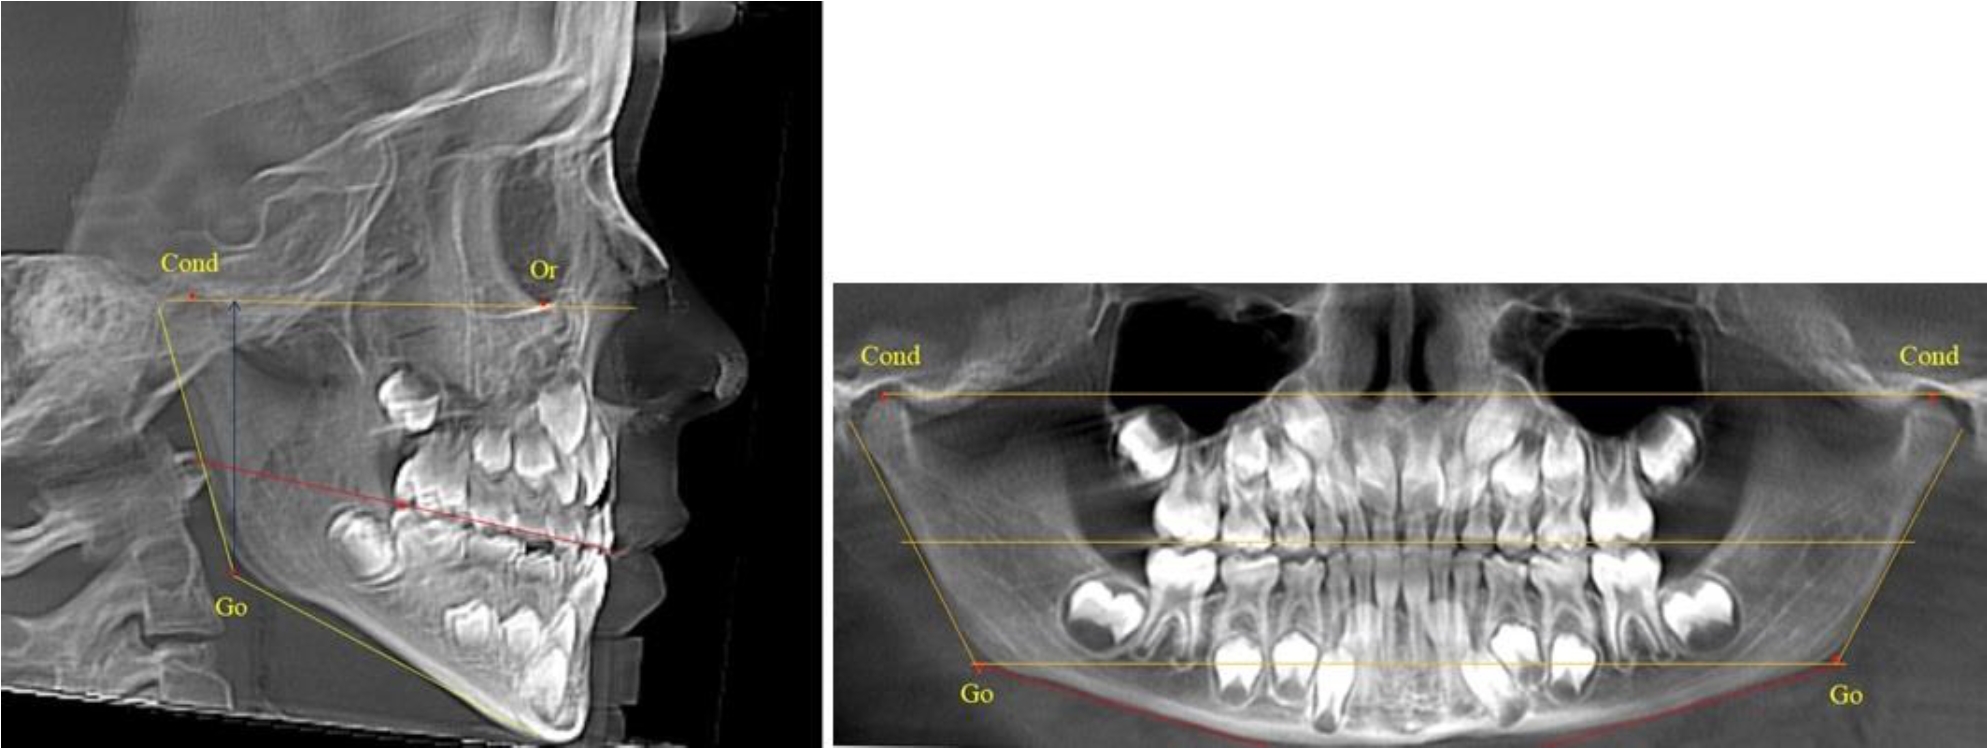

В 1-й группе были проанализированы 7 телерентгенограмм и 7 ортопантомограмм, что составило (6,60 ± 2,41) % от числа изученных рентгенограмм. На всех парах рентгенограмм угол нижней челюсти, измеренный на телерентгенограмме, соответствовал углу, полученному при построении угла на ортопантомограмме. Окклюзионная линия практически однотипно делила ветвь на два отдела (рис. 1).

Как на ортопантомограмме, так и на телерентгенограмме высота ветви у детей в периоде сформированного прикуса молочных зубов составляла (42,21 ± 2,48) мм. При этом высота верхней окклюзионно-суставной части была (22,57 ± 1,46) мм, а нижней – (19,64 ± 1,54) мм.

Учитывая вариабельность абсолютных величин, определи относительные показатели соразмерности частей ветви нижней челюсти. Так, отношение высоты верхней части ветви к нижней в среднем составляло 1,15 ± 0,13. Отношение общей высоты ветви к верхней ее части составляло 1,87 ± 0,14, а отношение общей высоты ветви к нижней ее части было 2,14 ± 0,16 и достоверных различий по относительному показателю отношения всей высоты к верхней и нижней челюсти нами не отмечено (р ˃ 0,05). При этом визуально обе части выглядели примерно равноразмерными.

Рис. 1. ТРГ и ОПТГ пациента 1-й группы

В 5-й группе были проанализированы 14 комплектов рентгенограмм, что составило (13,21 ± 3,29) % от общего числа. На всех рентгенограммах отмечен очередной этап подъема высоты прикуса, обусловленный прорезыванием вторых постоянных моляров. Окклюзионная линия делила ветвь на два отдела (рис. 5).

Рис. 5. ТРГ и ОПТГ пациента после смены молочных зубов и прорезывания вторых постоянных моляров

Высота ветви у детей 5-й группы составляла (62,87 ± 3,62) мм, что было достоверно больше, чем у детей других групп (р ˂ 0,05). При этом высота верхней окклюзионно-суставной части была (40,23 ± 2,01) мм, а нижней – (22,64 ± 1,78) мм. Высота верхней части была вдвое больше нижней, что и определяло особенности соразмерности частей ветви нижней челюсти в анализируемый возрастной период.

Относительные показатели соразмерности частей ветви нижней челюсти показали, что отношение высоты верхней части ветви к нижней в среднем составляло 1,78 ± 0,18. Отношение общей высоты ветви к верхней ее части составляло 1,56 ± 0,12, а отношение общей высоты ветви к нижней ее части было 2,78 ± 0,14, что и определяло особенности соразмерности частей ветви нижней челюсти в анализируемый возрастной период.